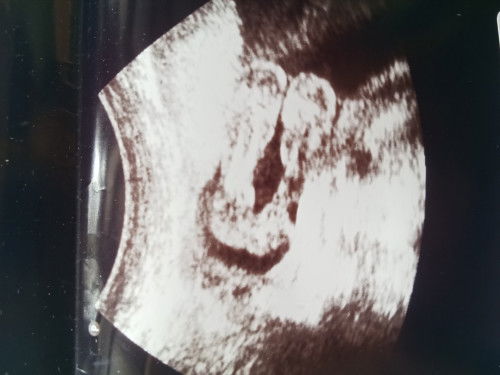

เเบบนี้เพศอะไรหรอคะะ

คุณหมอให้ใบซาวด์มาค่ะเราท้องเเรกมองไม่ออกเลยค่ะ น้องเป็นเพศหญิงหรือเพศชายคะ #ขอบคณสำหรับคำตอบล่วงหน้านะคะ